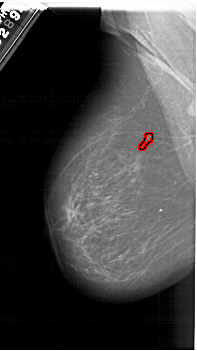

A_1276_1.LEFT_MLO

LEFT_MLO LINES 6301 PIXELS_PER_LINE 3541 BITS_PER_PIXEL 12 RESOLUTION 43.5 OVERLAY

FILE: A_1276_1.LEFT_MLO.OVERLAY

TOTAL_ABNORMALITIES 1

ABNORMALITY 1

LESION_TYPE CALCIFICATION TYPE PLEOMORPHIC DISTRIBUTION CLUSTERED

ASSESSMENT 4

SUBTLETY 4

PATHOLOGY BENIGN

TOTAL_OUTLINES 1

BOUNDARY